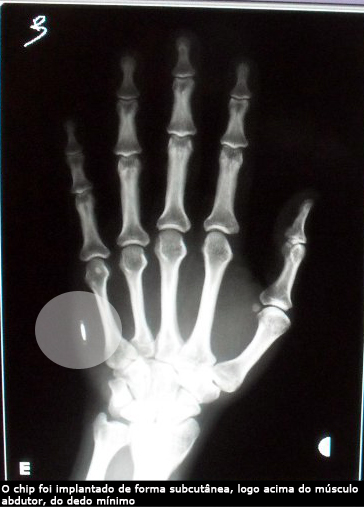

Imagem retirada do site do IFSC-USP

Vantagens e desvantagens à parte, sem dúvida é uma ideia muito interessante. Mário Gazziro, doutorando do Instituto de Física de São Carlos (IFSC/USP) e docente do Instituto de Ciências Matemáticas e da Computação (ICMC/USP), está desenvolvendo este projeto em que ele mesmo foi a "cobaia" ao implantar o chip na mão.